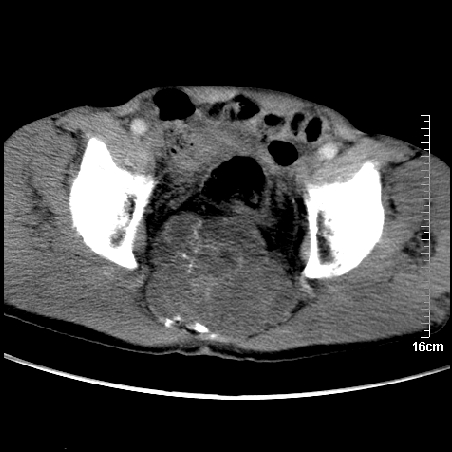

标题: CT16886:骶尾部占位:1.脊索瘤?2.巨细胞瘤? [打印本页]

标题: CT16886:骶尾部占位:1.脊索瘤?2.巨细胞瘤?

平扫:

部分骶尾骨已被软组织密度的肿瘤所取代,同意“首先考虑脊索瘤,不除外转移瘤”的意见。

1、骶尾部巨大软组织肿块,部分骶尾骨以被软组织肿块代替,呈不规则侵蚀;病变突向盆腔内;增强扫描病变呈不均质强化;首先考虑脊索瘤。不支持的一点就是病变内无钙化。